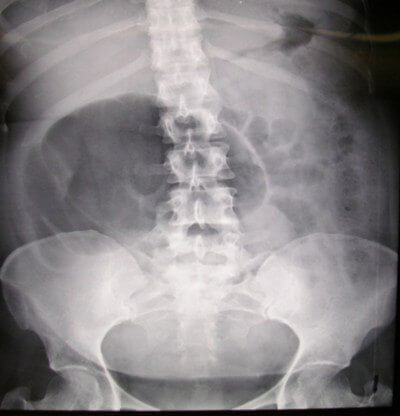

El Dr. Philipp Mitteroecker, del Departamento de Biología de la Universidad de Viena, afirma que es un tema importante para comprender la evolución humana. “¿Cuál es el motivo de que los problemas relacionados con el parto, en particular lo que llamamos la pelvis estrecha, sean tan altos?”, cuestiona.

Es una cuestión que lleva sobre la mesa mucho tiempo. Esta no es otra que por qué la pelvis no ha aumentado en el curso de la evolución humana. El tamaño de la cabeza de un bebé humano es grande en comparación con otros primates. Los monos, por ejemplo, tienen partos generalmente sin problemas.